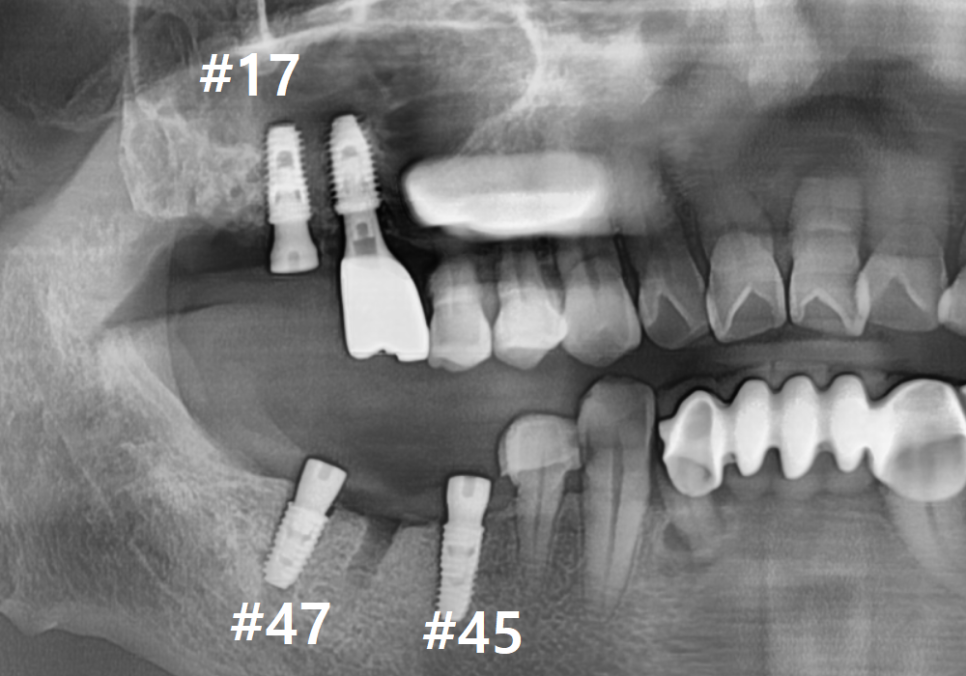

입안을 꼼꼼히 살펴보니 맨 끝 어금니(#47)는

이미 오래전에 뽑으신 상태였고

세 개의 치아(#44~46)를 하나로 묶은

브릿지를 쓰고 계셨습니다.

자세히 살펴보니, 잇몸 쪽으로

치아 뿌리가 살짝 드러나 있고

그 틈으로 음식물이

끼어있는 모습이 관찰되었죠.

엑스레이를 찍어보니 상황은

생각보다 더 심각했습니다.

보철 내부가 이미 다 삭아서

치아 머리와 뿌리가 툭 끊어져 있는 상태였거든요.

뿐만 아니라, 오른쪽 위 어금니(#18,17) 주변도

염증 때문에 잇몸 뼈가 많이 녹아있는 상태였습니다.